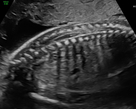

Differenzierte Fehlbildungsdiagnostik

Diese weiterführende feindiagnostische Untersuchung wird zwischen der 20. – 24. Schwangerschaftswoche durchgeführt.

In der Regel wird für diese Untersuchung eine Überweisung vom betreuenden Frauenarzt ausgestellt, z. B. wenn im Rahmen der üblichen in den Mutterschaftsrichtlinien empfohlenen Ultraschalluntersuchung eine Auffälligkeit gesehen wurde. Weitere Gründe für eine Überweisung sind Risikoschwangerschaften oder auch der Wunsch der Eltern nach einer zusätzlichen Absicherung. Neben der allgemeinen Entwicklung des Kindes können hier –noch genauer als im Ersttrimesterscreening – alle Organe des ungeborenen Kindes begutachtet werden. Zusätzlich wird mittels Dopplersonographie die kindliche Versorgung und die des Mutterkuchens überprüft. Da Herzfehlbildungen zu den häufigsten angeborenen Fehlbildungen gehören, stellt die detaillierte fetale Echokardiographie (Untersuchung des kindlichen Herzens) einen wichtigen Bestandteil der Untersuchung dar. Dabei werden sowohl die Anatomie des Herzens als auch die Blutflüsse begutachtet.